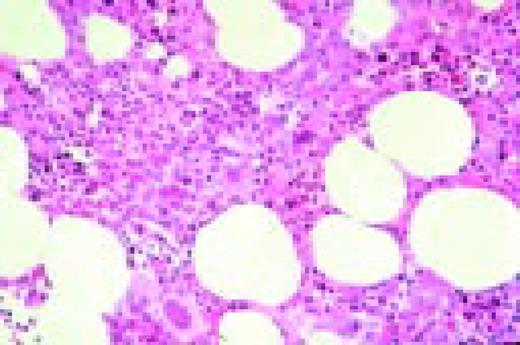

Slide L53

Hodgkin's disease associated with AIDS, bone marrow biopsy, H&E. Total replacement of normal bone marrow by an abnormal infiltrate including two Reed-Sternberg cells (top right).FIG53